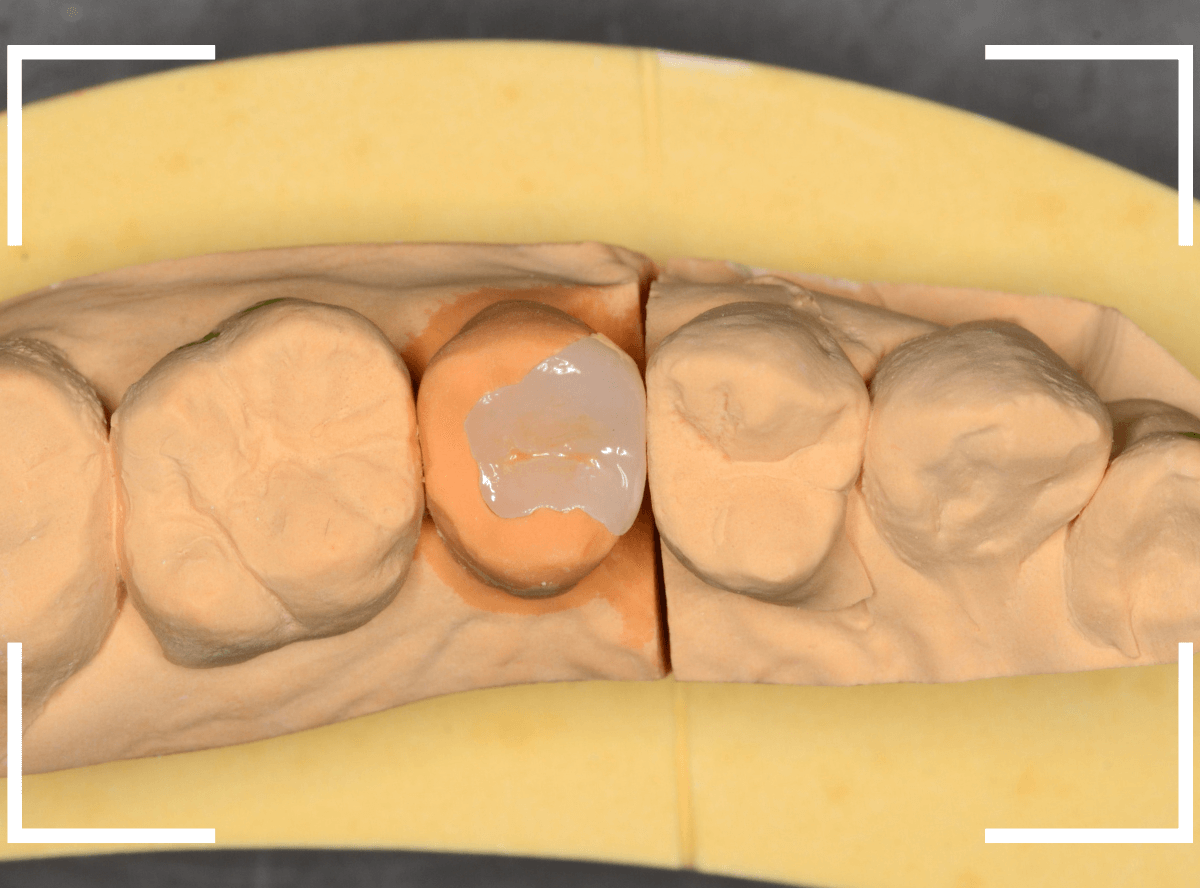

模型上で精密に製作します。

模型上でしっかりと作製します。

模型上の様子です。

模型上ではこのような形になります。

今回も、模型上でしっかりと製作します。

模型上で精密に作ります。

模型上で、しっかりと製作します。

丁寧に型どりをして、模型上でジルコニア・インレーを製作します。

模型上で、精密に歯の形を作製します。

あらかじめ撮影したお口の中の写真を参考に、模型上で、ジルコニア・インレーを製作します。